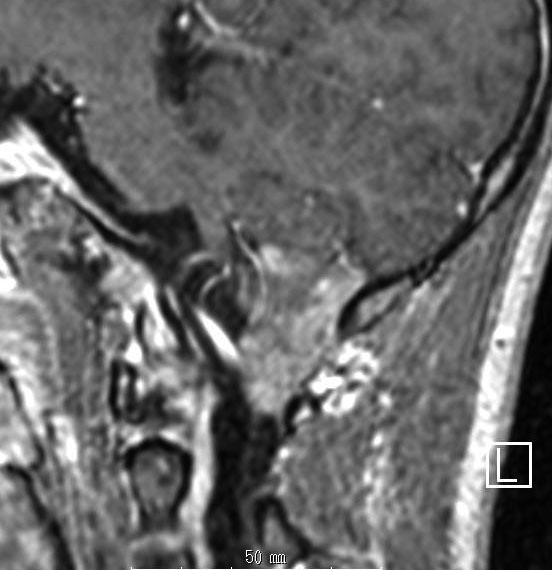

第4脳室上衣腫(良性と言える思春期例:EPN-PFB)

青年に発生したものです。かなり分化度の高い延髄背側 ovex 発生の上衣腫です。境界が明瞭なのですが,実際に側方(延髄小脳脚槽)で椎骨動脈や後下小脳動脈,下位脳神経に癒着しているので剥離は必ずしも容易ではありません。この例では幸い全摘出できました。

摘出した標本のHE染色です。左側ではperivascular pseudorosette(血管周囲の無核野)がみられ,右側ではependymal tube (ependymal canal) が認められます。

左がGFAP染色、右がMIB-1(Ki-67)染色です。 GFAPは腫瘍血管の周囲の無核野に強陽性です。MIB-1 labelling index が1%以下であり,この上衣腫の増殖能が極めて低いことを示しています。このような高分化型で増殖能の低い上衣腫は脊髄髄内には多いのですが,脳では珍しいものです。ovex中心上衣腫にみられます。